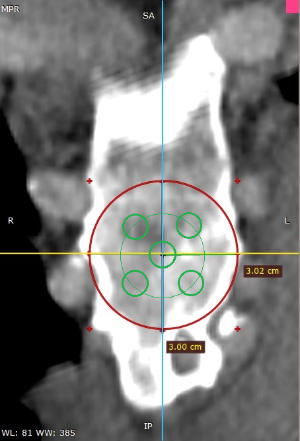

Pectus Excavatum Pectus Excavatum Asimétrico Índice de Asimetría 0.6 (+R/-L)(|AI|> 0.05 Asimétrico) Índice de Haller 4.5 (HI >3.5) Índice de Corrección 49.13% Rotación esternal 18.1 ° (a la derecha)

Informe de evaluación del TAC de un paciente enviada al cirujano